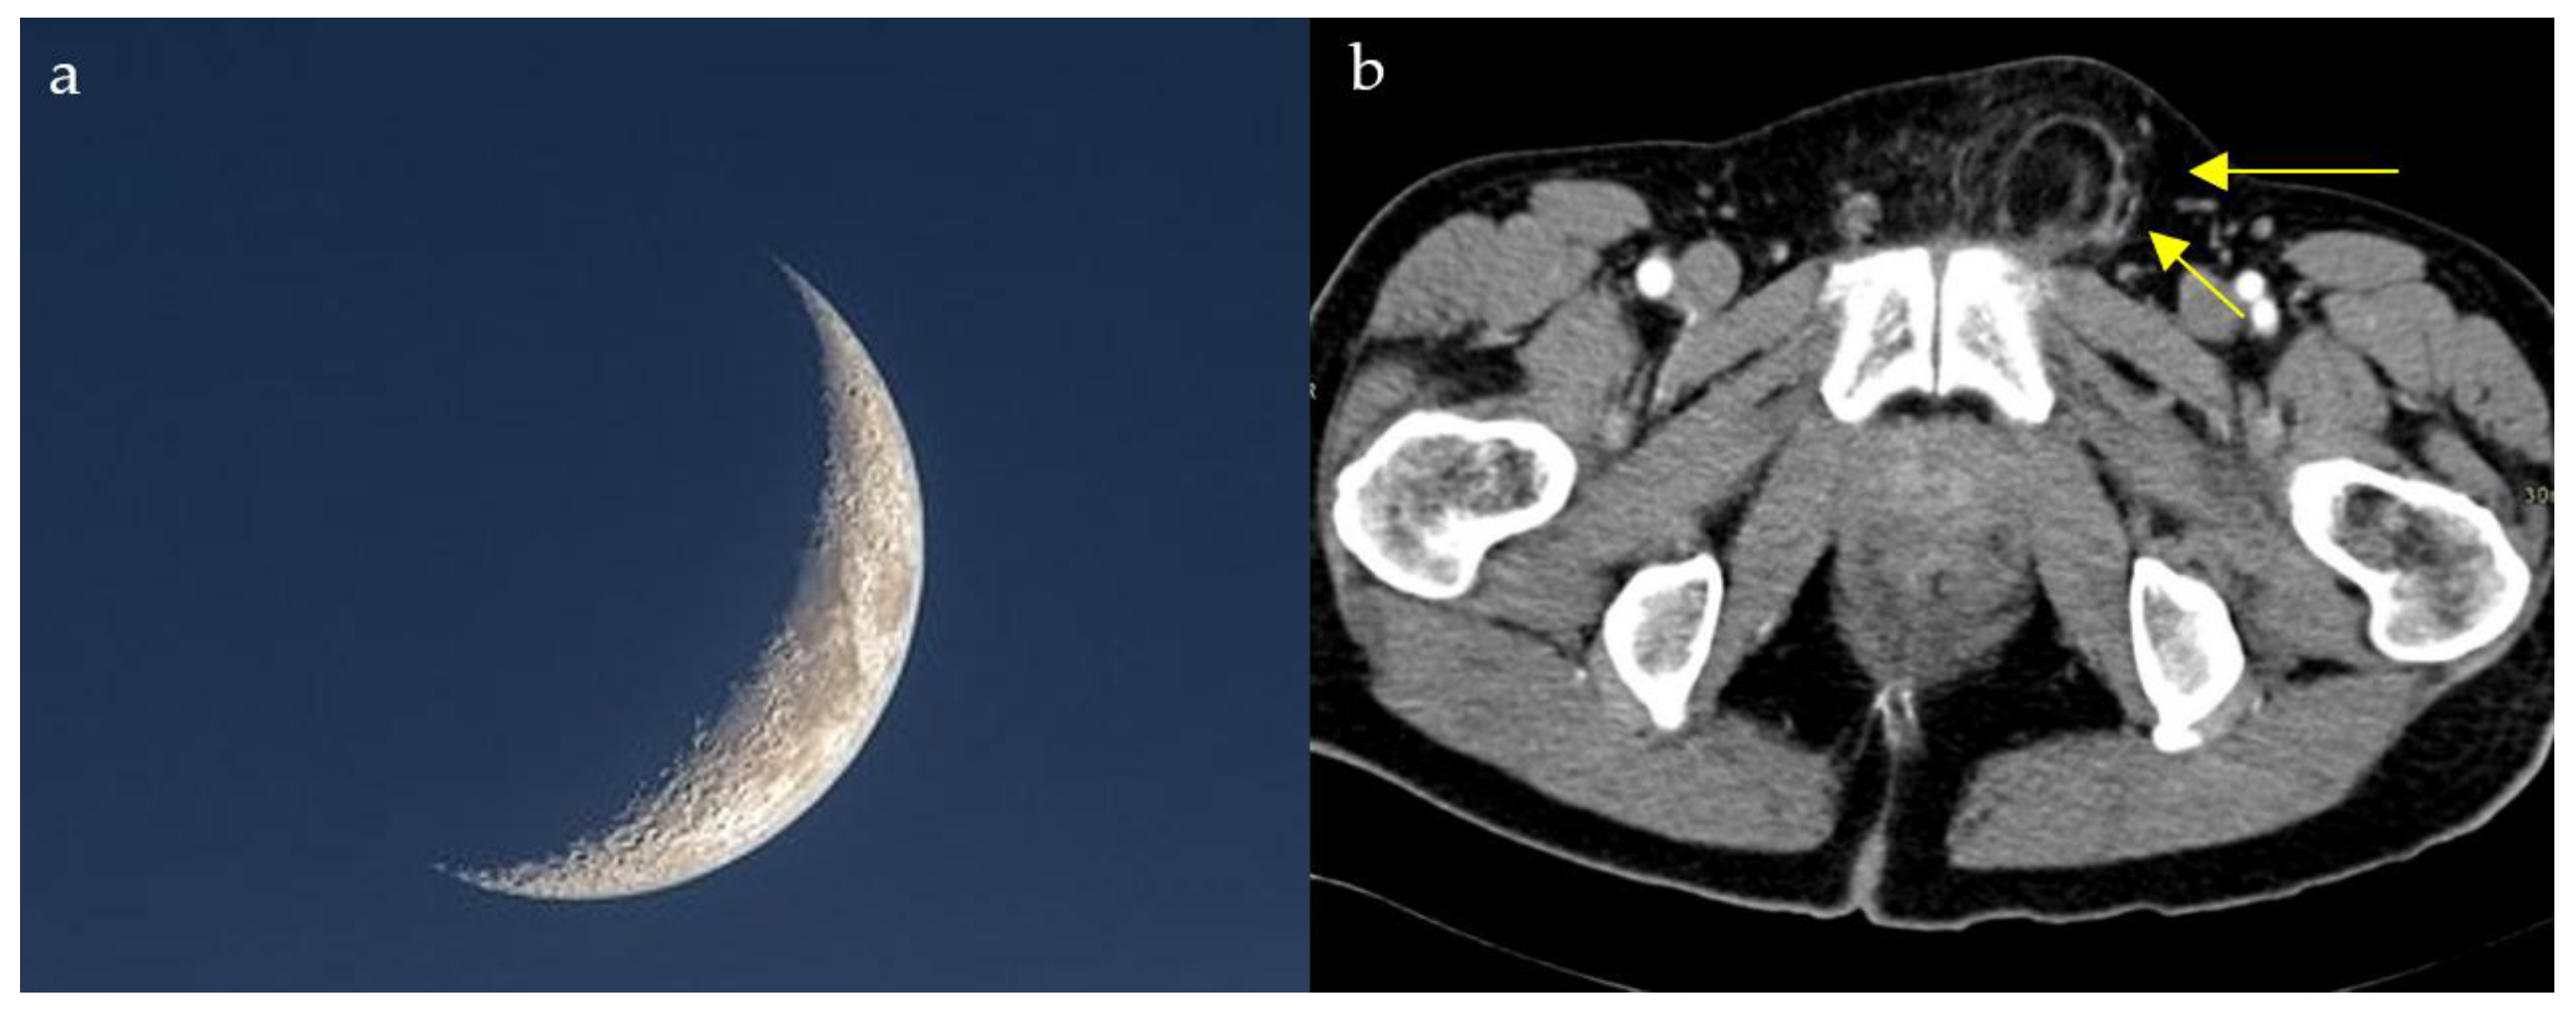

2.4. Loss of Half-Moon Overlap Sign

2.13. Lateral Crescent Sign

- Burkhardt, J.; Arshanskiy, Y.; Munson, J.; Scholz, F. Diagnosis of Inguinal Region Hernias with Axial CT: The Lateral Crescent Sign and Other Key Findings. Radiographics 2011, 31, E1–E12. [Google Scholar] [CrossRef]

- Hasbahceci, M.; Erol, C. Usefulness of Computed Tomography for Differentiation of Primary Inguinal Hernia. Gazi Med. J. 2015, 26, 170–173. [Google Scholar]